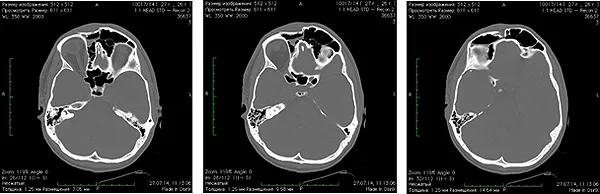

Spiral computed tomography before surgery: